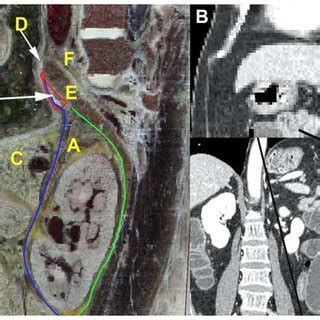

Lesser Omentum Diagram / The left lateral view of the upper abdomen showing the ... / The diagram shows this rotation with spinal cord at the top, vertebral body then dorsal aorta then pertioneal wall and cavity.

The diagram shows this rotation with spinal cord at the top, vertebral body then dorsal aorta then pertioneal wall and cavity.